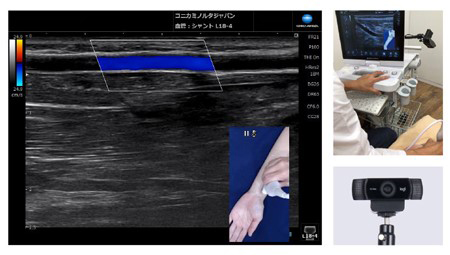

超音波画像とカメラ画像を同時表示Camera Link

カメラで撮影した映像を診断中の超音波画像に重ねて表示。表示した画像は静止画と動画(音声情報も保持可能)で保存できます。後から検査状態を確認する際や,情報共有に便利です。

※オプション機能